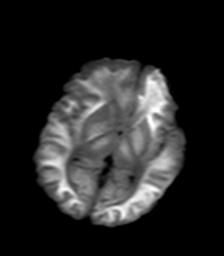

发热、头痛伴精神异常1周

较对称性脑白质异常信号,深部白质t2明显低信号(铁质沉积过多?)

考虑脑白质病变,请结合临床病史及实验室检查进一步分析。